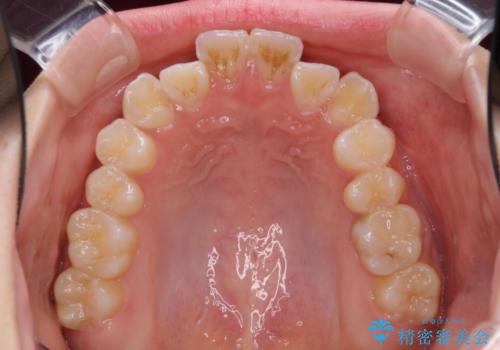

- 海外留学の予定があるが、学生のうちに歯列を整えたいとのことで来院された患者様です。

前歯にデコボコがあり、口元がやや突出した印象があったため、IPR(歯と歯の間を削る)と親知らずを抜歯した上での歯列全体の後方移動をメインに、インビザラインを用いて矯正治療を行うこととしました。